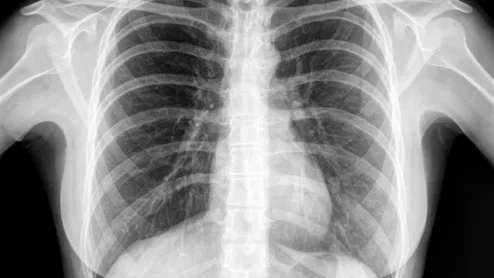

AI models can be trained to evaluate chest x-rays as well as radiologists, according to a new study published by Radiology. Specialist-approved reference standards played a crucial role in the team’s research.